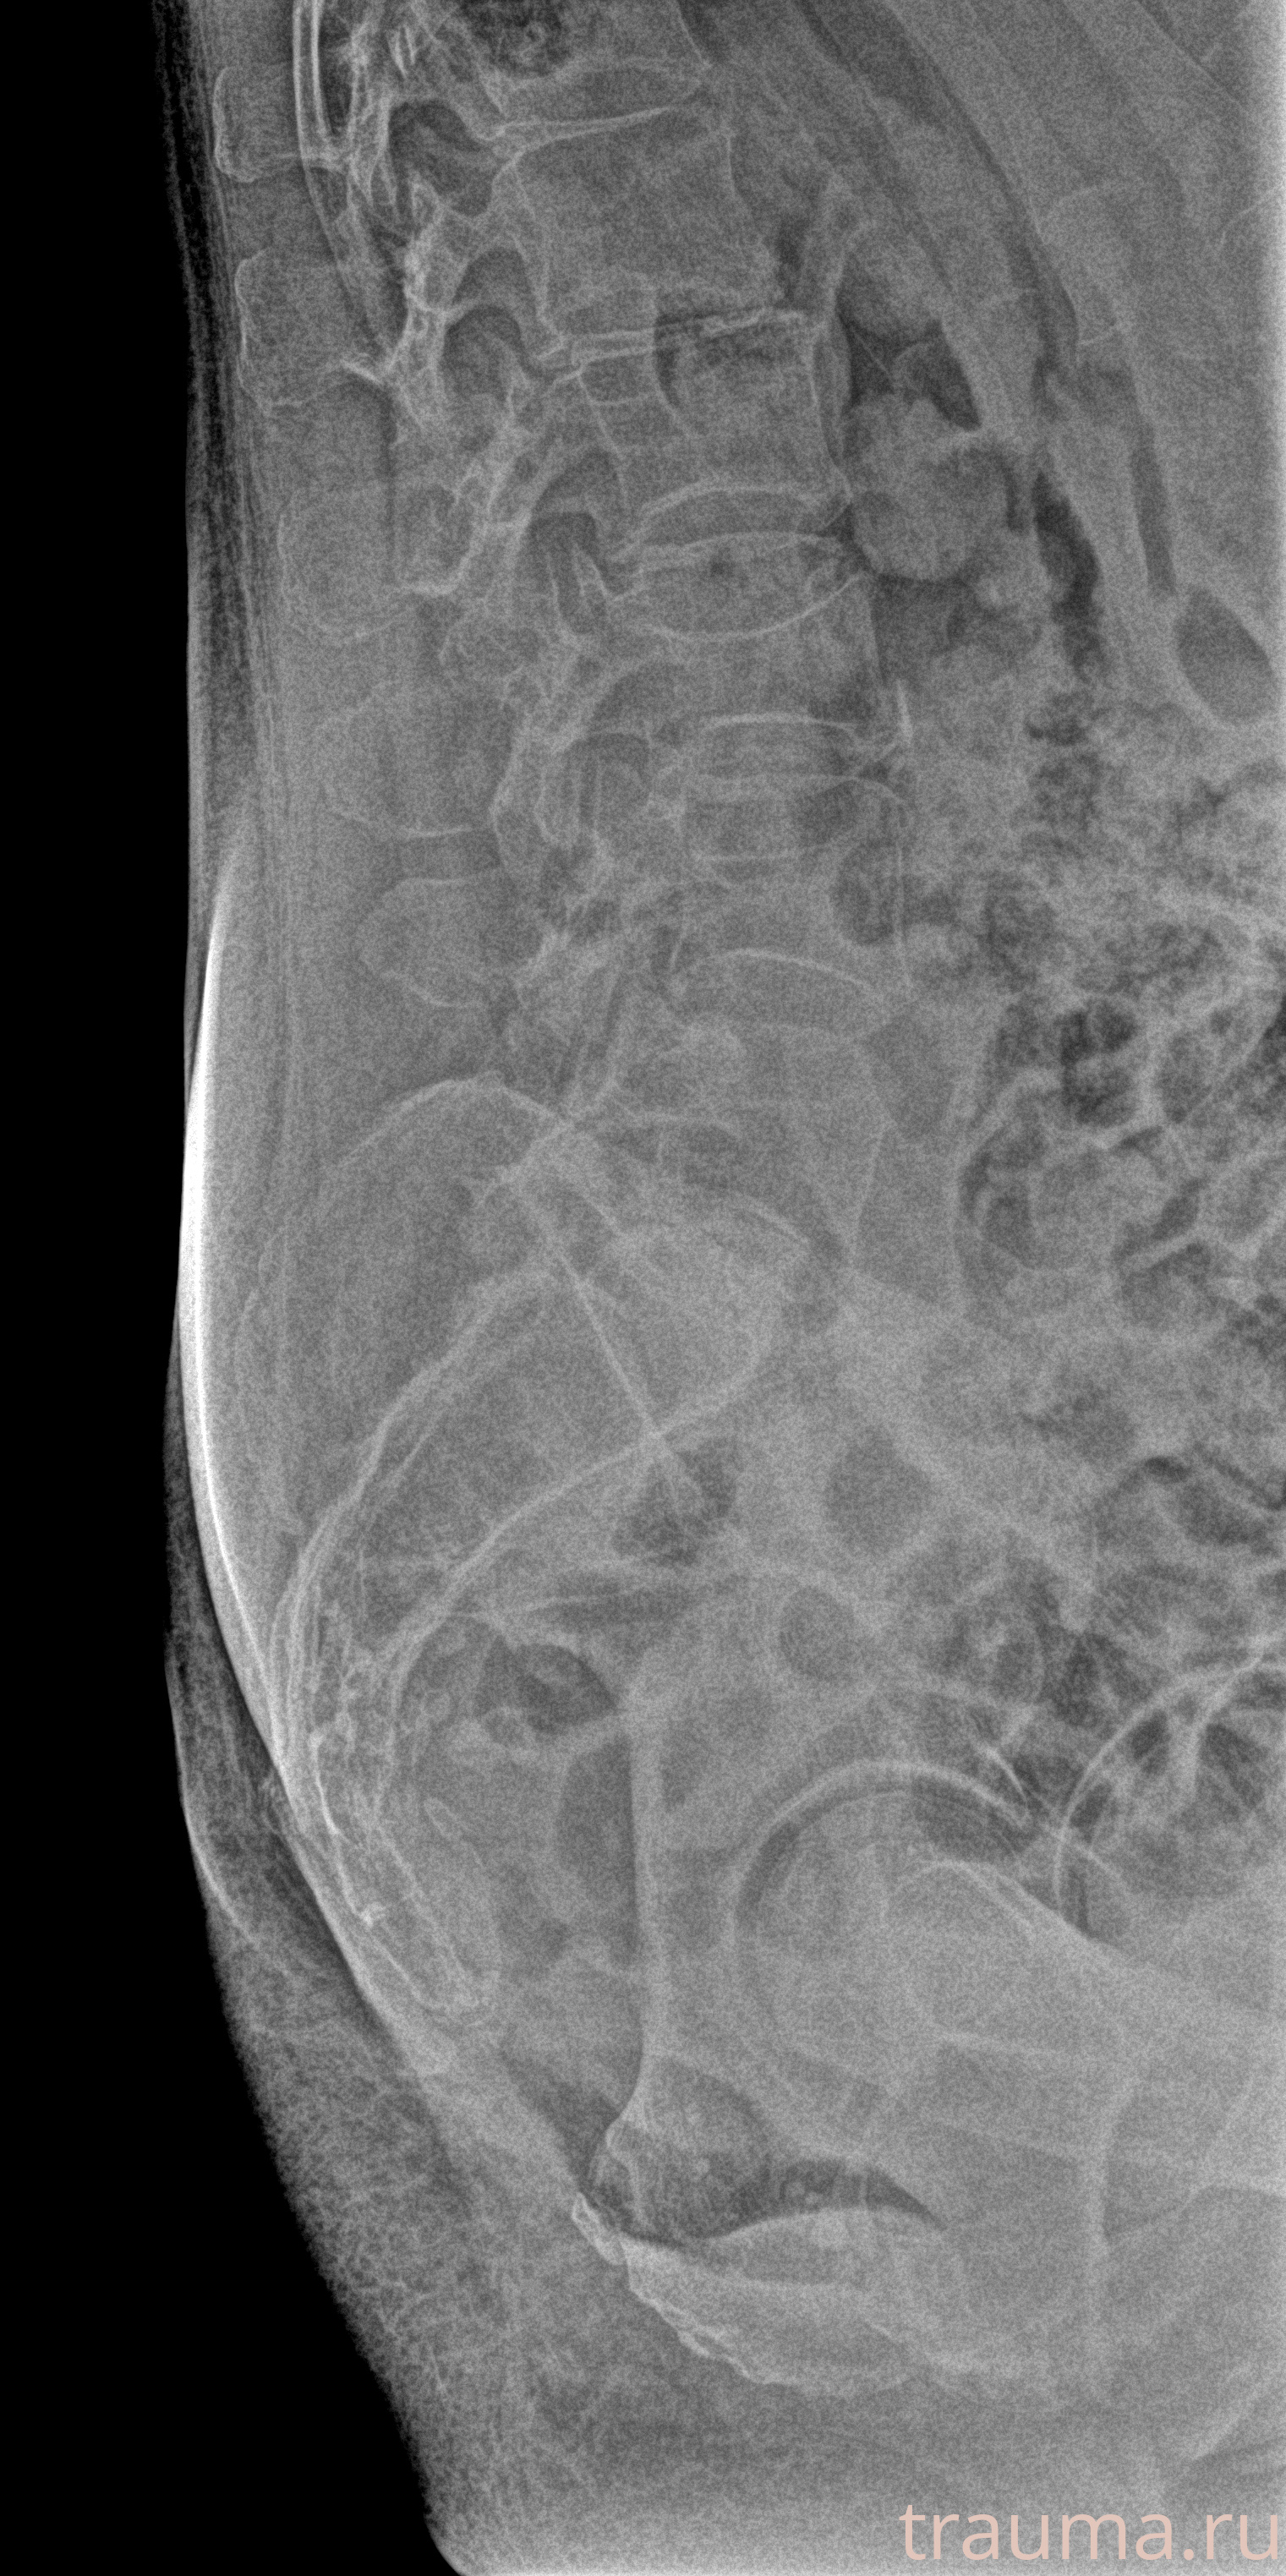

Рентгенограммы

Рентген на дому: по вашему адресу приезжает врач-рентгенолог, травматолог-ортопед с мобильным рентгеновским аппаратом, проводит диагностику травмы или заболевания, делает необходимые рентгенограммы, дает рекомендации по дальнейшему лечению. Получить качественные снимки в домашних условиях возможно благодаря уникальной методике, разработанной МосРентген Центром для института  Склифосовского